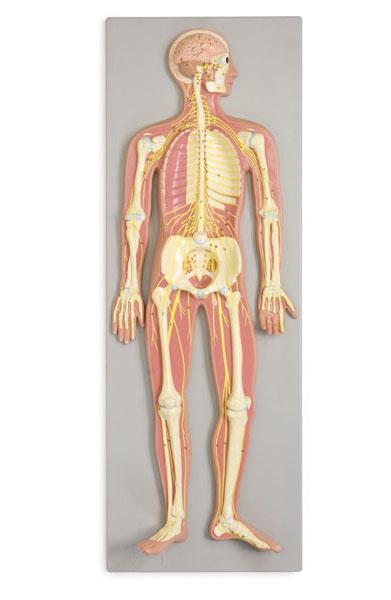

Reliéfny model – Nervový systém. Rozmery: 90x32x11 cm. Váha: 3700 g. Tento model reliéfu v polovičnej veľkosti ukazuje všeobecný prehľad na periférny a centrálny nervový systém človeka: hlava je otvorená, s mozgom a mozočkom; dráha hlavných nervov je dobre znázornená vo vzťahu k kostre.

Reliéfny model – Nervový systém

Reliéfny model – Nervový systém v polovičnej veľkosti.